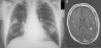

Se extrajeron 2 hemocultivos (medio aerobio y anaerobio) y se inició tratamiento empírico con piperacilina-tazobactam. La antigenuria de neumococo y Legionella fueron negativas. Tras 4días de tratamiento antibiótico sin mejoría se realizó una TC toracoabdominal en la que se confirmaban los hallazgos radiológicos previos sin otras alteraciones. En ambos hemocultivos se aisló Rhodococcus equi, cambiándose el tratamiento, según antibiograma, a imipenem, rifampicina y gentamicina. Tras 10días de ingreso el paciente comenzó con cefalea e inestabilidad, realizándose RMN cerebral (fig. 1B), en la que se observaban 8 lesiones nodulares subcentimétricas corticosubcorticales compatibles con abscesos cerebrales.

Se mantuvo el tratamiento intravenoso 2meses y se continuó con azitromicina y trimetoprim-sulfametoxazol oral 4meses más. Tras 2semanas de tratamiento la clínica respiratoria había desaparecido y la radiografía de tórax era normal. Al mes los hemocultivos fueron negativos, con desaparición de la clínica neurológica. La RMN cerebral de control a los 3meses fue normal.